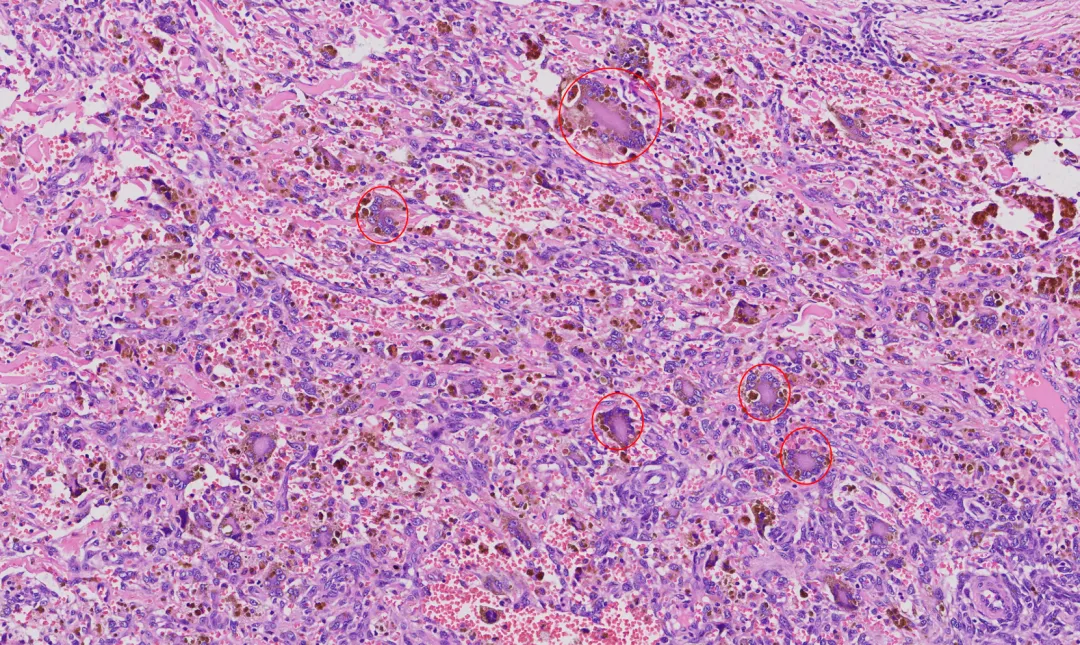

①肿瘤组织内有不规则的类似于血管腔的出血性裂隙。

③细胞内外含铁血黄素的沉积。

a.上皮样 / 梭形细胞结节:片状 / 巢状排列,胞质丰富嗜酸,核轻度异型。

b.假血管瘤样腔隙:腔隙充满血液,无内皮衬覆(关键)。

c.厚纤维假包膜:伴含铁血黄素沉积。